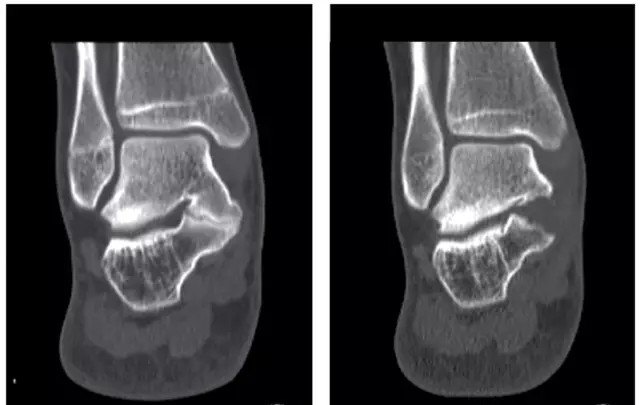

踝关节镜下切除跟距骨桥